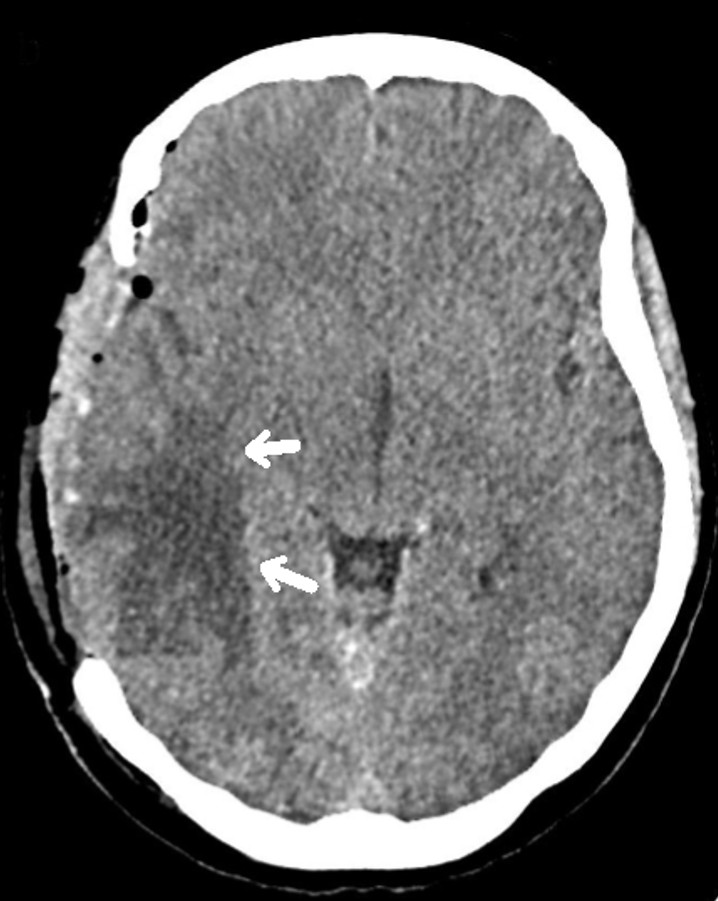

A 17-year-old female patient presented to the emergency department with complaints of severe headache for 1 week and slowed movements and left extremity weakness that started 1 day ago. Physical examination revealed a body mass index of 26 kg/m2, an obese appearance, and signs of hirsutism. In vital signs, blood pressure was 120/75 mmHg, pulse rate was 70 beats/minute, and temperature was 36.7°C. Neurological examination revealed consciousness and central facial paralysis on the right, muscle strength was 2/5 in the left lower and upper extremities, and other system examinations were normal. Glasgow Coma Scale was 10. Papilledema was detected. Laboratory findings included hemoglobin: 10.2 g/dL, MCV: 83.5 fL, platelet count: 13,000/mm3, WBC: 3350/mm3, and absolute neutrophil count: 1750/mm3, sodium: 135, potassium: 3.8, creatinine: 0.68. Prothrombin time: 13 seconds, D-Dimer: 3.3 was high. Brain tomography performed at an external center revealed no pathology. Magnetic resonance imaging (MRI) of the brain performed in our center at his presentation to us with complaints of increased headache and weakness revealed changes compatible with diffuse thrombus in the right transverse sinus, sigmoid sinus and jugular vein (Figure 1), signal increase and oedema compatible with venous hemorrhagic ischemia in the supratentorial right temporal, right basal ganglia and thalamic region (Figure 2), and changes suggestive of right to left shifting and uncal herniation. When her history was questioned, it was learnt that she had no previous thrombosis and no known systemic disease, and she had been using OCS containing 0.02 mg ethinylestradiol and 3 mg drospirenone for 1 year due to oligomenorrhoea. The patient underwent anterior temporal lobectomy and thrombectomy with urgent surgical decompression due to diffuse thrombus, shifting, and herniation findings, and altered consciousness on brain MRI (Figure 2)